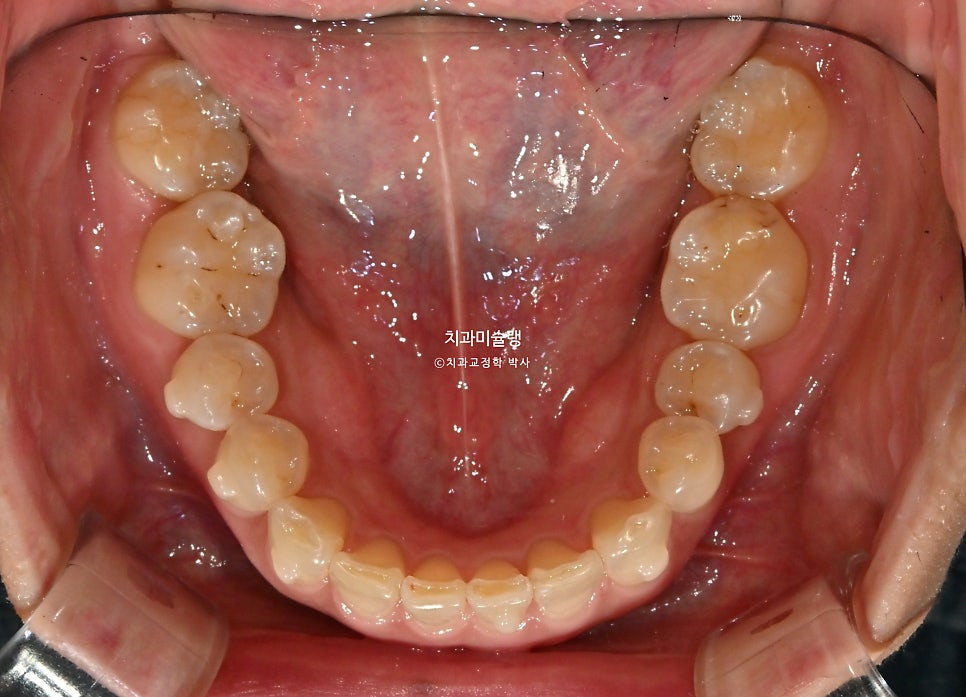

초진 시 구강 상태 분석

환자기준 우측 치아들이 내려와 있습니다. 앞니가 깊게 물리는 과개교합 입니다. 중심선 불일치도 보입니다.

어금니 교합은 좋은편.

앞니가 삐뚤합니다.